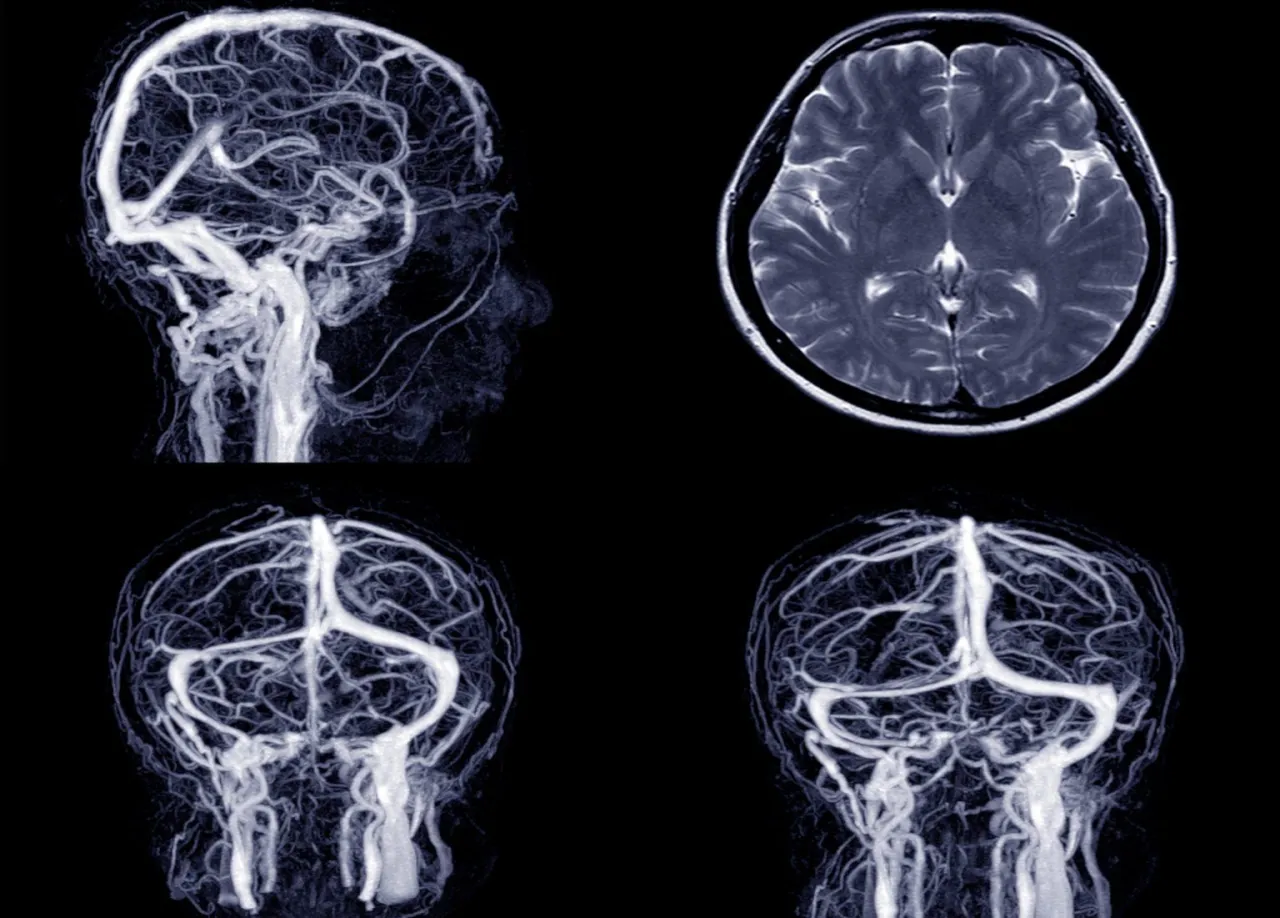

Tomografia komputerowa (TK) głowy to zaawansowana metoda diagnostyki obrazowej, która wykorzystuje promieniowanie rentgenowskie do tworzenia szczegółowych, przekrojowych obrazów struktur wewnątrzczaszkowych. W mojej ocenie, jest to nieocenione narzędzie, szczególnie w diagnostyce neurologicznej i urazowej, ponieważ pozwala na szybkie i precyzyjne "zajrzenie" do wnętrza głowy. Tomograf, obracając się wokół pacjenta, wykonuje serię zdjęć rentgenowskich pod różnymi kątami, które następnie komputer przetwarza w trójwymiarowy obraz mózgu, kości czaszki, zatok i naczyń krwionośnych.

Choroby naczyniowe mózgu stanowią poważne zagrożenie dla zdrowia, a tomografia komputerowa, zwłaszcza w specjalistycznej formie angio-TK, jest w stanie je skutecznie wykrywać. Pozwala ona na identyfikację tętniaków poszerzeń naczyń krwionośnych, które mogą pęknąć i spowodować krwotok oraz malformacji naczyniowych, czyli nieprawidłowych połączeń między tętnicami a żyłami. Te schorzenia często rozwijają się bezobjawowo, stanowiąc "ciche zagrożenie", dlatego ich wczesne wykrycie jest tak ważne.

Kiedy mówimy o szczegółowej ocenie naczyń mózgowych, nie sposób pominąć angio-TK. To specjalna odmiana tomografii, podczas której podaje się środek kontrastowy dożylnie, a następnie wykonuje serię szybkich skanów. Pozwala to na stworzenie szczegółowej, trójwymiarowej mapy naczyń krwionośnych mózgu, co umożliwia precyzyjną ocenę ich struktury, wykrycie zwężeń, niedrożności, tętniaków czy malformacji. Jest to badanie o ogromnej wartości diagnostycznej w przypadku chorób naczyniowych.